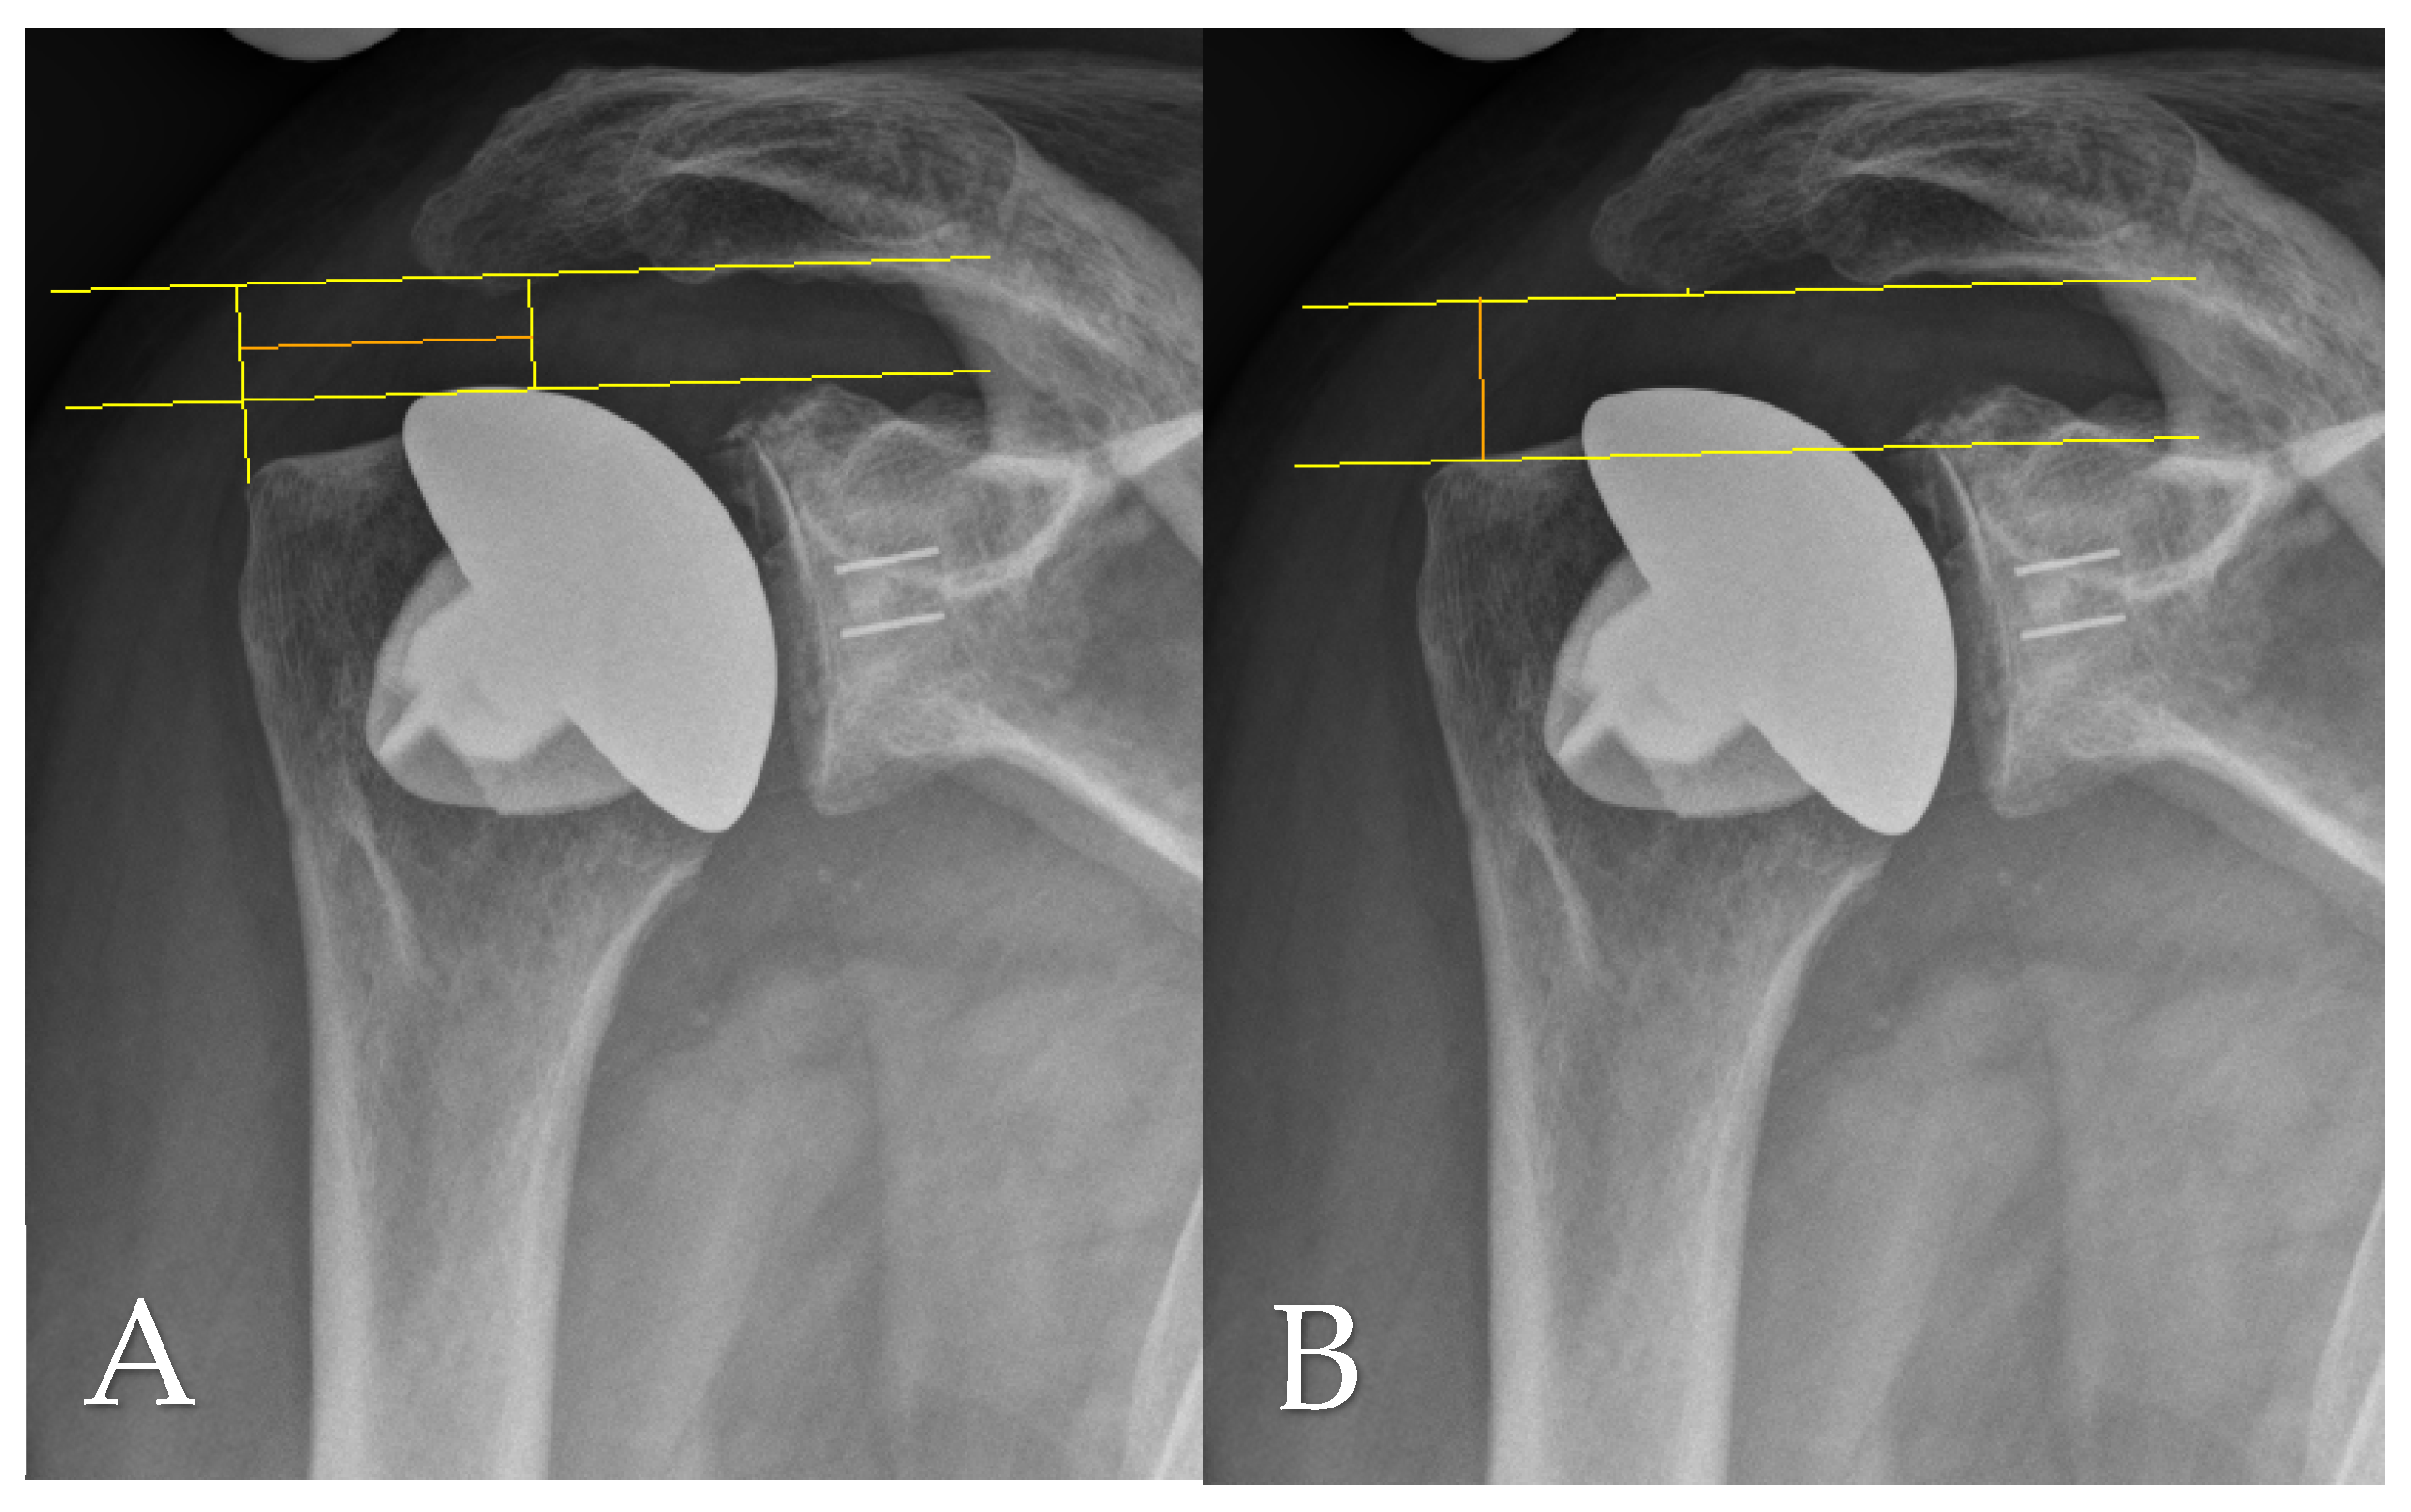

2.4. Radiographic Assessment